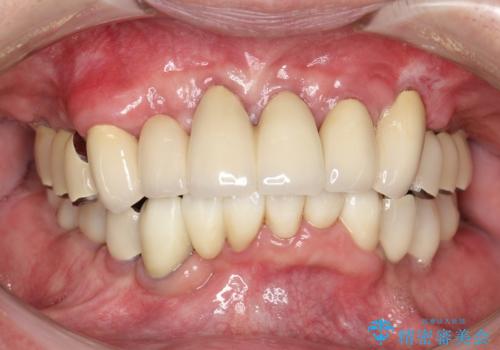

[フルジルコニアクラウン] 老朽化した銀歯を白く